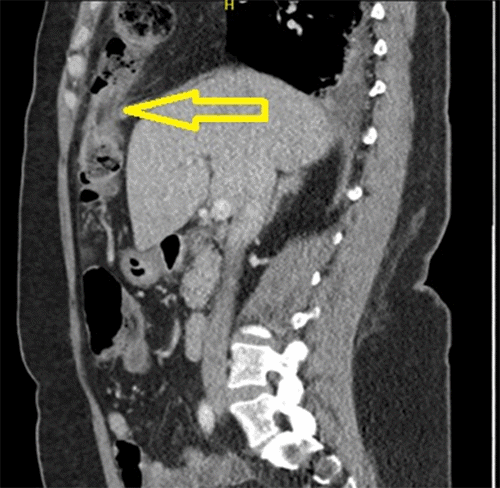

The patient is a 50-year-old woman who presented to the emergency department (ED) with a three-day history of epigastric pain and two days of nausea, vomiting, and obstipation. Her symptoms worsened approximately 12 hours prior to presentation. She reported having undergone a robotic-assisted laparoscopic total abdominal hysterectomy with bilateral salpingo-oophorectomy (TAH-BSO) for a uterine fibroid on the same day the epigastric pain began. Moreover, she also reported having a five-year history of less severe, similar pain, which always resolved spontaneously; she believed this episode would do the same. She appeared in painful distress and showed significant epigastric tenderness upon physical examination. An abdominal and pelvic computed tomography (CT) scan was obtained in the emergency room, demonstrating a right anterior diaphragmatic hernia containing a loop of transverse colon (Figure 1). The defect was further associated with congestion and edema of the antimesenteric border of the herniated bowel (Figure 2).

Figure 2. CT Showing Incarcerated Morgagni Hernia. Published with Permission